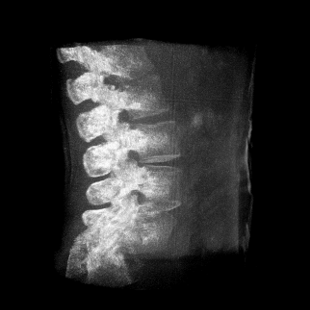

成像清晰、操作簡易、擺位便捷,主要適用于骨科、脊柱外科、矯形外科、創傷骨科及手術室等,能大幅度提升手術水準,降低手術風險和并發癥的概率。

術中三維成像和橫斷面圖像提供多角度的手術診斷信息,輔助醫生進行術中評估判斷,諸如骨折復位情況和內植入螺釘的尺寸和位置,輔助手術更好地完成。

提供更大的術中三維成像視野,采集更多圖像信息,可一次拍全全段頸椎、全段腰椎、七節胸椎、雙側骶髂關節、股骨頭及單側盆骨。